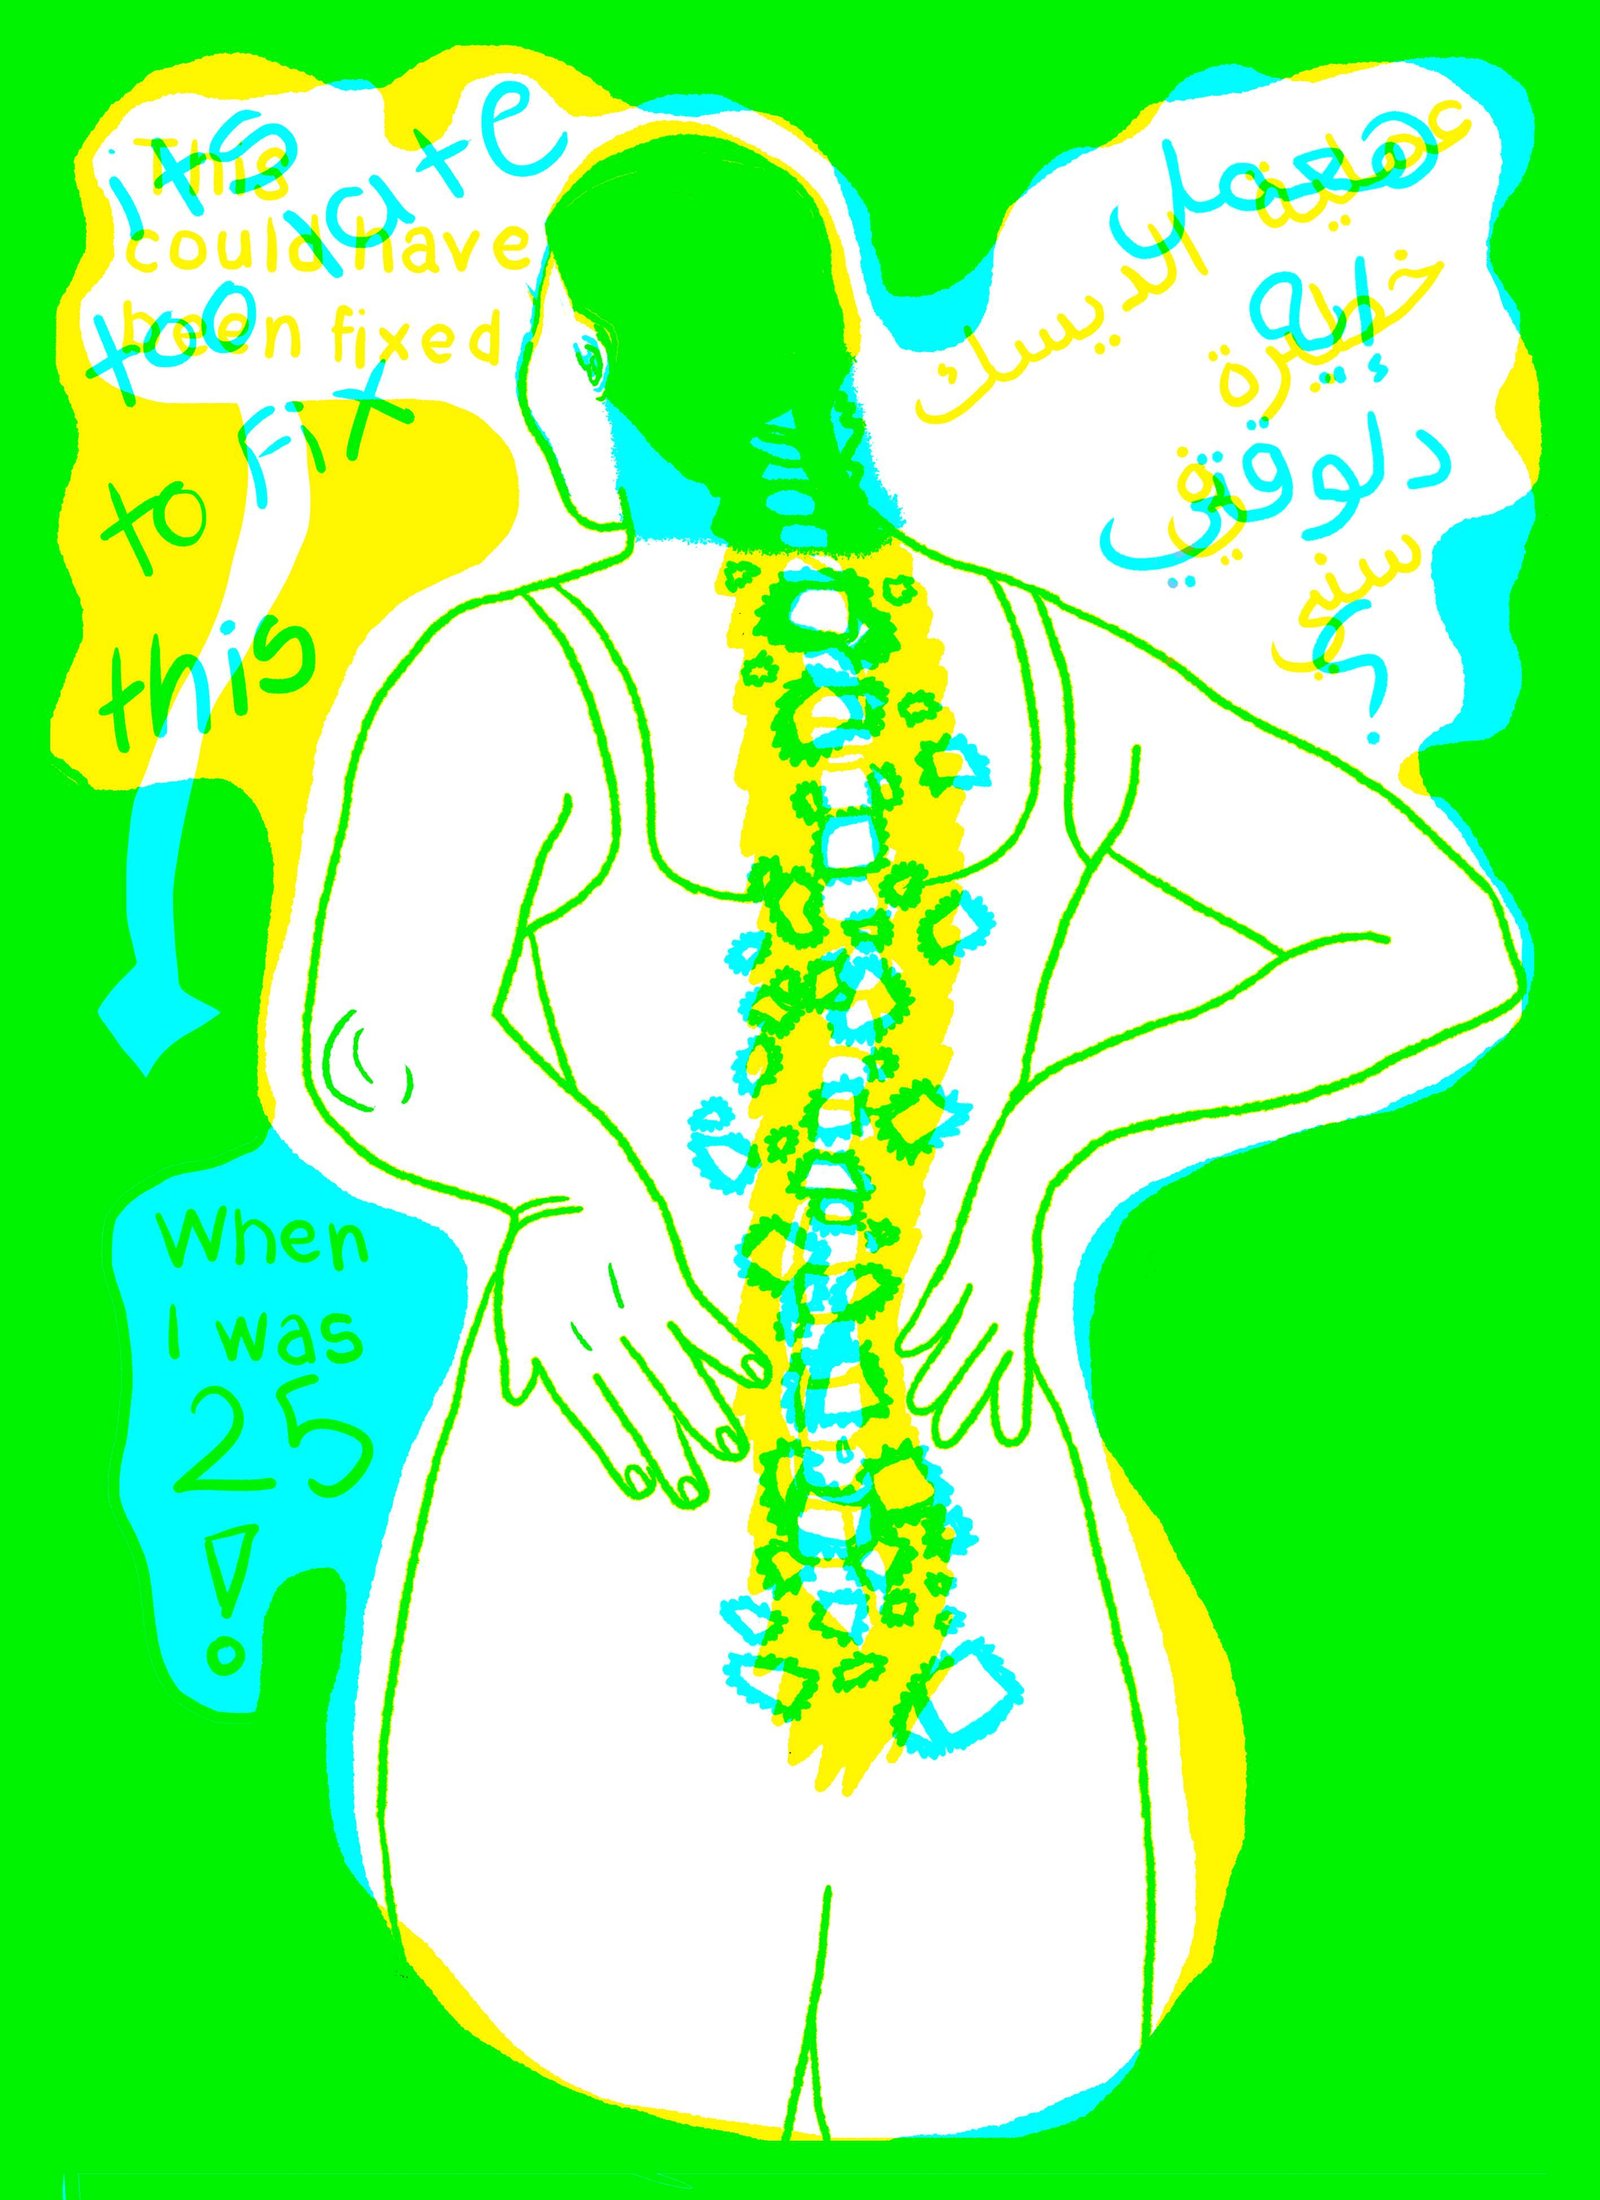

Red Filter - Second

The P.O.V of the doctor, the negative consequences that occurred.